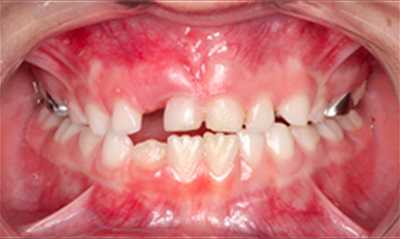

Mordida cruzada anterior

Caso 1

As imagens abaixo ilustram um caso de mordida cruzada anterior tratado com ortopedia facial. Observe que os incisivos superiores, que se encontravam inicialmente atrás dos incisivos inferiores, passou a ocluir corretamente.